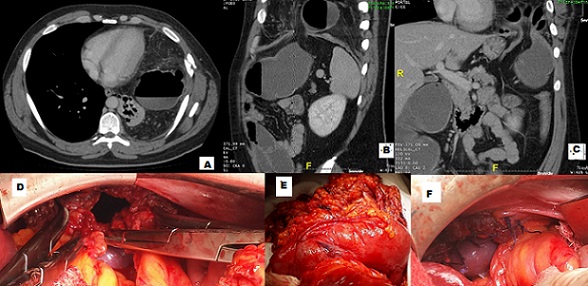

La hernie diaphragmatique post-traumatique constitue une lésion particulière en traumatologie car elle risque de passer inaperçue et peut représenter ainsi un piège diagnostique. Le diagnostic se fait alors à l'occasion d'une complication, en particulier l'étranglement. La coupole diaphragmatique gauche est la plus fréquemment touchée. Nous rapportons le cas d'un patient âgé de 28 ans qui a été victime d'une plaie par arme blanche basithoracique gauche il y a trois ans et la radiographie du thorax avait montré un hémothorax gauche minime ayant bien évolué sous simple surveillance. Le patient avait consulté pour un syndrome occlusif sans signe respiratoire. La tomodensitométrie avait objectivé une hernie diaphragmatique gauche étranglée contenant le colon transverse gauche et l'épiploon comblant ainsi la cavité pleurale homolatérale jusqu'à l'apex pulmonaire refoulant légèrement le médiastin et le poumon avec une atélectasie passive en regard. Cet étranglement était responsable d'une distension majeur du colon d'amont et des dernières anses iléales. Le patient était opéré en urgence par laparotomie ayant permis la réintégration du colon (qui était souffrant mais qui a récupéré) dans la cavité péritonéale, la résection de l'épiploon de mauvaise qualité et une réparation du défect diaphragmatique par raphie simple. L'évolution était favorable avec une sortie à J5 et un suivi sans particularités. L'éventualité de la survenue d'une hernie diaphragmatique doit être systématiquement présente à l'esprit en cas de traumatisme thoraco-abdominal fermé violent ou en cas de plaie basithoracique. Il est nécessaire de continuer la surveillance et de réaliser, au moindre doute, une exploration par une tomodensitométrie.